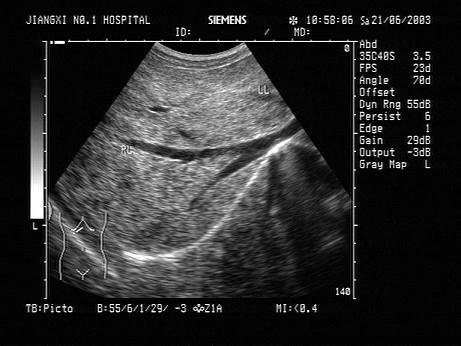

问题 男,48岁,肝区胀痛,脾肿大。结合超声声像图,诊断为?(?)

选项 A.肝血管瘤 B.肝脓肿 C.肝癌 D.血吸虫肝纤维化 E.脂肪肝

答案 D